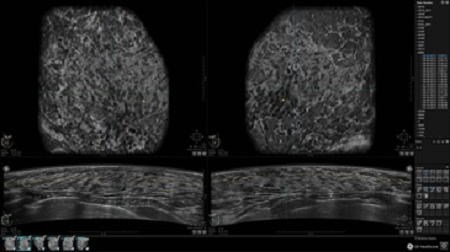

• Получение объемных 3D изображений с возможностью покадрового просмотра

• Отображение объемных 3D ультразвуковых изображений, которые состоят из традиционных поперечных и воссозданных коронарных и сагиттальных проекций

• Многооконный просмотр: 4 - 12 изображений

• Стандартизованная ориентация изображения: «толстый срез» в коронарной плоскости; поперечная; сагиттальная плоскость; радиальный и антирадиальный поворот изображения; просмотр исключительно области интереса

• Изменяемая толщина среза: 0,5 - 10,0 мм (шаг 0,5 мм)

• Срез: 0,5 - 2,0 мм (шаг 0,5 мм)

• Одновременный просмотр двух изображений для сопоставления в коронарной плоскости